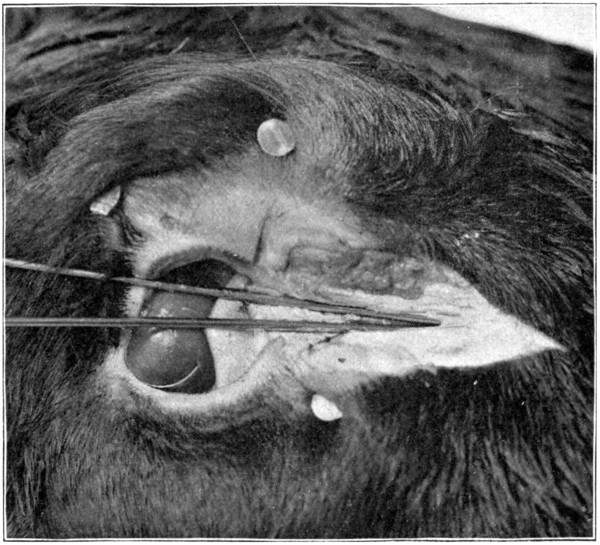

Fig. 45—Showing only a part of a calf’s head and the knitting-needles inserted in the puncta. (Page 94.)

Fig. 46.

Be supplied with two knitting-needles. Take one, lubricate its full length with a little vaseline, lard, oil, or any other lubricant. Insert the needle into the punctum of the[93] lower lid, and push it downward and forward, aiming to come out in the nose a short distance from its end. At first it may be a little difficult to get the needle started; if so, just wiggle the needle, pushing it at the same time as directed, until the nasal duct is found. Do not remove the needle. To insert the other[94] needle into the punctum of the upper lid is rather difficult; for that reason the punctum of the lower lid was chosen, first. Grease the needle, as was done to the first one, and, with a little patience and careful manipulation, the canal opening and its course will soon be found. The needle may then be pushed through until it meets the first one. (Fig. 45.)[95] From the puncta lacrimalia to the place of meeting of the two needles, marks the course of the two canaliculi and their junction before they merge and form the nasal duct. Leave the needles where they are, and begin cutting away the skin. The needles will then mark the course of each canal and the duct very plainly. With the small scissors the canals and the duct may be loosened from the surrounding tissues. Or, the scalpel may be used to lay open the canals, cutting along over the top of the needles. (Fig. 46.)